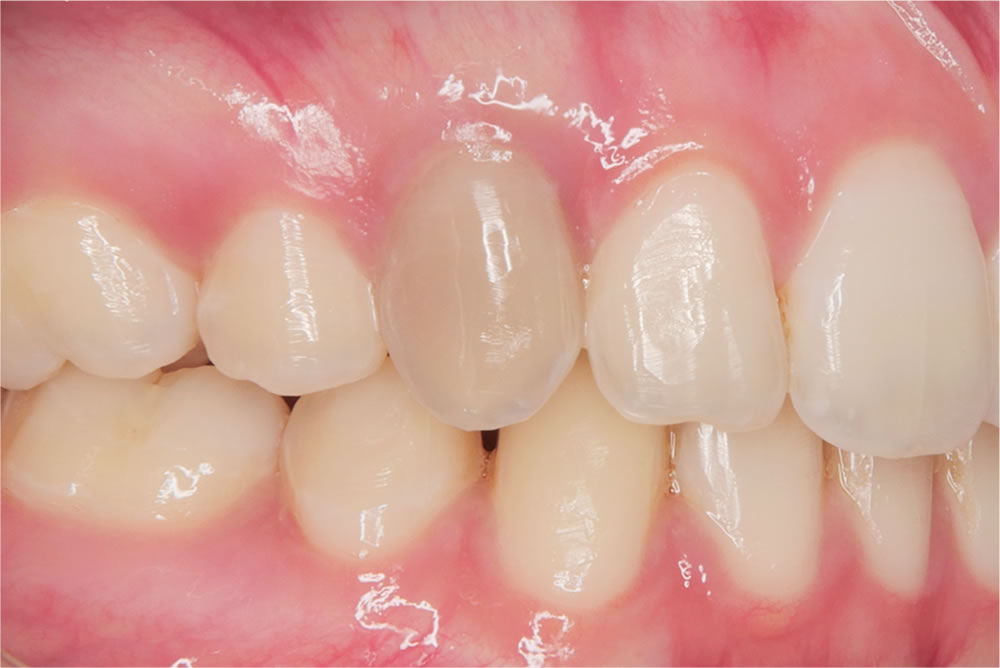

根管治療が終了した後、患者さんの主訴であった黒ずんでしまった前歯の色に対して治療を行いました。

通常、このように神経が死んで変色した歯に対しては、大きく削ってセラミックの被せ物を入れる方法が一般的です。

しかし当院では、患者さんの歯をできるだけ守るため、削らずに漂白する「インターナルブリーチ」を提案しました。歯の内部に過酸化水素の薬剤を入れることで、神経が失活して黒くなった歯でも内側から白くすることができます。

今回の患者さんも2回の薬剤の交換(約2ヵ月)の治療で歯の色が完全に回復し、自然で美しい白さを取り戻すことができました。患者さんからも「こんなに白く戻ると思わなかった」と非常に満足していただけました。